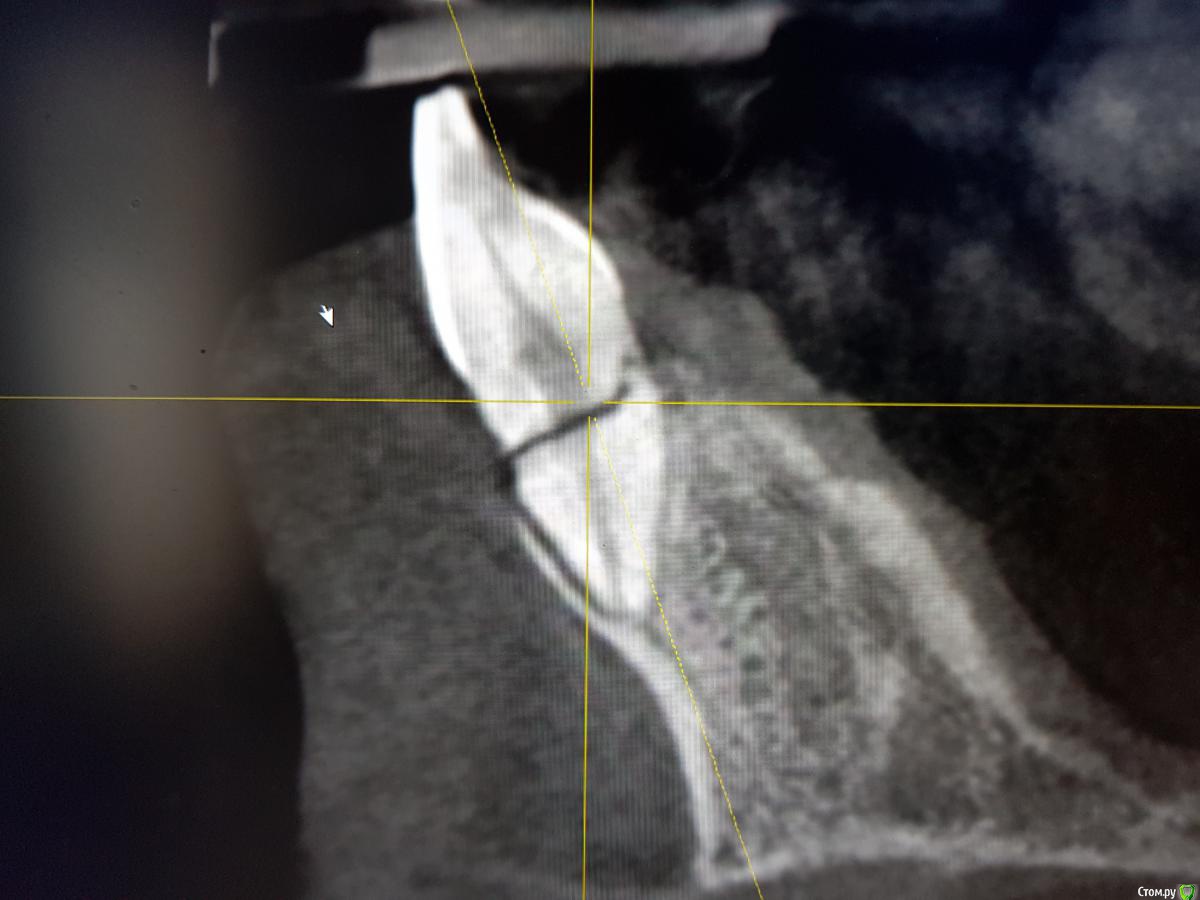

Kazankov.Egor Опубликовано 25 сентября, 2018 Поделиться Опубликовано 25 сентября, 2018 (изменено) Травма, фактура 11,21. Вопрос: одномоментно или отсроченно (НКР в момент удаления). Что смущает в одномоментной постановке:1) как заглубить имплантат, если использовать титановую сетку (поставить ниже уровня зенитов соседних зубов и край верхний край зафиксировать небно, т.е. фактически засыпать их наглухо или фиксировать мембрану от уровня платформы?)2) как это всё ушить правильно.3) те ли вопросы я задаю) Изменено 25 сентября, 2018 пользователем Kazankov.Egor Ссылка на комментарий

Kazankov.Egor Опубликовано 25 сентября, 2018 Автор Поделиться Опубликовано 25 сентября, 2018 Когда была травма? Какие жалобы? Status localis? Я за репозицию и шинирование. Травма около месяца назад, зубы подвижны (1-2 степень), слизистая бледно-розового цвета, влажная, свищевой ход в области 11 зуба. Ссылка на комментарий